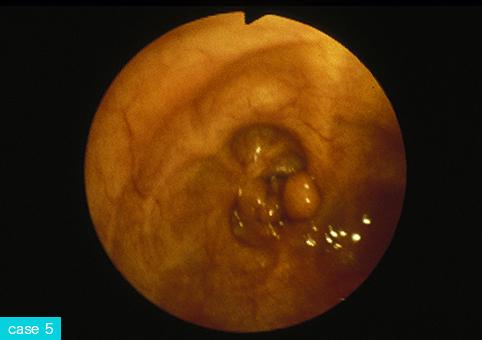

질환(병리주체)의 분류 종양양 병변/염증성 용종증

부위(장기별) 대장/상행

검사방법 내시경

종양의 최대경(밀리미터) 1~9